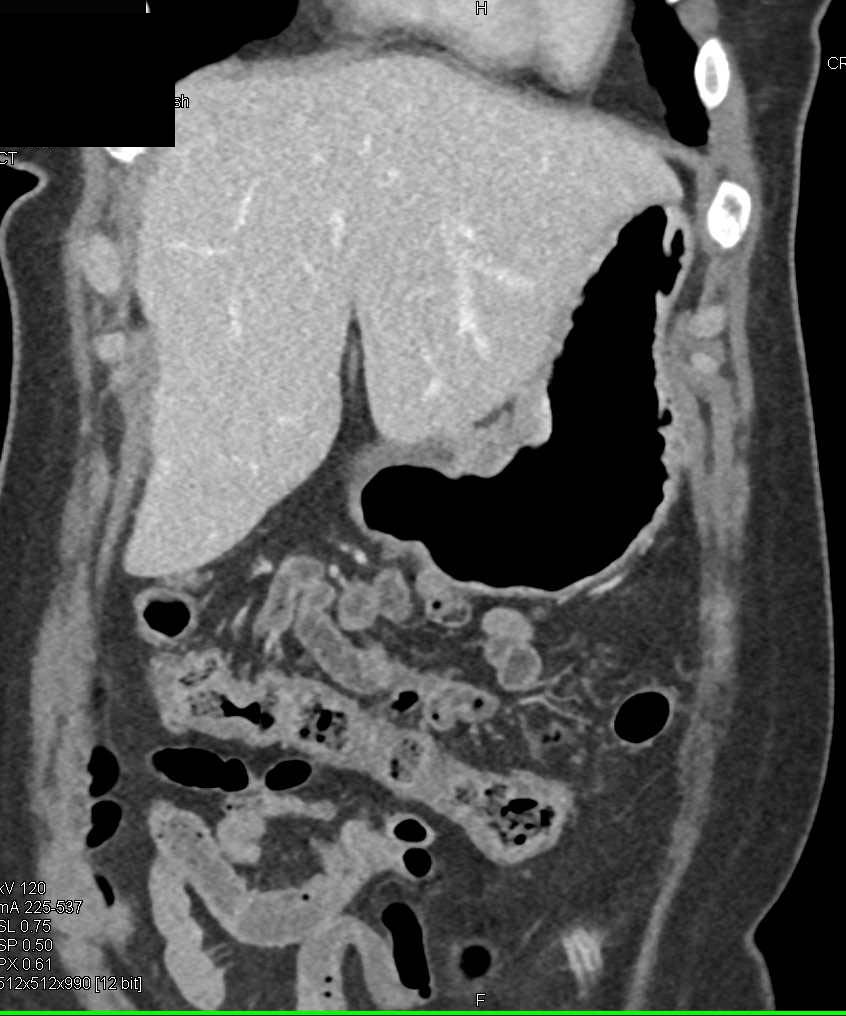

Stomach cancer CT – wikidoc

Gastric Cancer with Extensive Adenopathy – Stomach Case Studies …

Carcinoma of the Gastric Antrum – Stomach Case Studies – CTisus CT Scanning

Gastric Cancer with Extensive Adenopathy – Stomach Case Studies …

Gastric Cancer at the EG Junction – Stomach Case Studies – CTisus CT …

Ulcerating Gastric Cancer – Stomach Case Studies – CTisus CT Scanning

Gastric Cancer with Adenopathy – Stomach Case Studies – CTisus CT Scanning

Recurrent Gastric Cancer – Stomach Case Studies – CTisus CT Scanning

Gastric GIST Tumor – Stomach Case Studies – CTisus CT Scanning

Imaging Findings of Gastric Carcinoma | IntechOpen

Stomach Cancer On Ct Scan

Gastric Carcinoma | Radiology Key